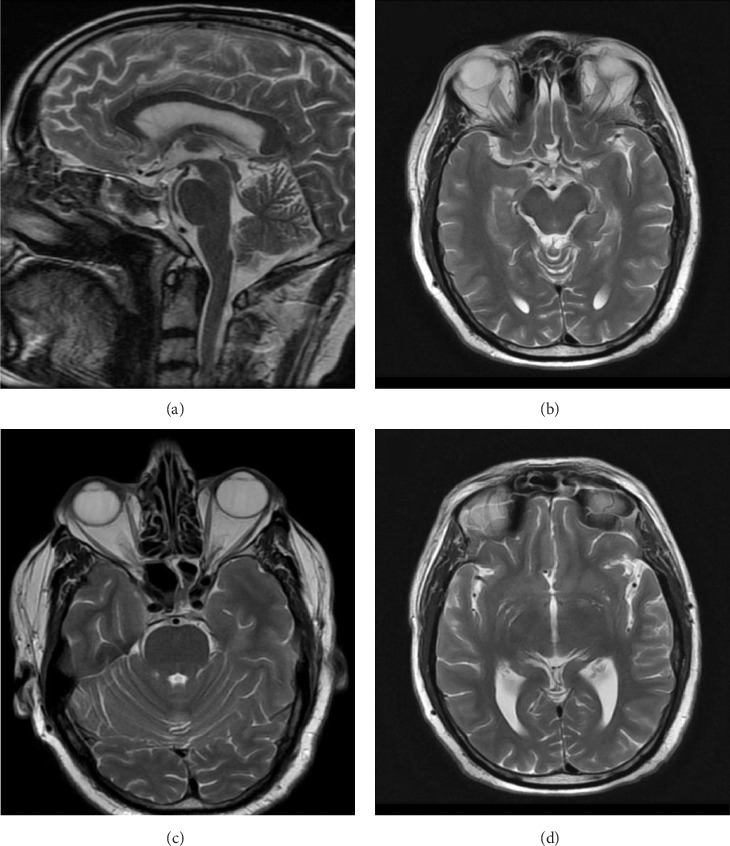

背景:奥赛罗综合症(OS)是一种罕见的精神障碍,其特征是妄想嫉妒和毫无根据的怀疑不忠。它与神经系统疾病如帕金森病(PD)有关,特别是在接受多巴胺激动剂(DAs)治疗的患者中。病例介绍:一名长期诊断为PD的69岁男性,由于不耐受而从左旋多巴/卡比多巴转向罗匹尼罗后出现OS。在开始使用罗匹尼罗6个月后,患者开始对妻子的忠诚产生强烈的妄想,尽管没有认知能力下降或精神病史。妄想症状使他的婚姻关系严重紧张。临床表现及诊断评估:神经学检查与PD相符,核磁共振(MRI)未见脑结构异常。罗匹尼罗使用与症状发作之间的时间相关性导致了罗匹尼罗诱发OS的诊断。罗匹尼罗在4周内逐渐停用,并引入喹硫平。患者的精神症状明显改善,妄想信念消除,配偶关系恢复。结论:该病例强调了da(包括罗匹尼罗)在PD患者中诱导OS的潜力。临床医生应在PD治疗过程中对精神病学副作用保持警惕,并考虑及时干预,包括药物调整和抗精神病治疗,以防止严重的社会心理后果。

Background: Othello syndrome (OS) is a rare psychiatric disorder characterized by delusional jealousy and unfounded suspicions of infidelity. It has been associated with neurological diseases such as Parkinson's disease (PD), particularly in patients receiving dopamine agonists (DAs). Case Presentation: A 69-year-old man with a longstanding diagnosis of PD developed OS after transitioning from levodopa/carbidopa to ropinirole due to intolerance. Six months after initiating ropinirole, the patient began experiencing intense, delusional beliefs regarding his wife's fidelity, despite no cognitive decline or psychiatric history. The delusional symptoms significantly strained his marital relationship. Clinical Findings and Diagnostic Assessment: Neurological examination remained consistent with PD, and no structural brain abnormalities were observed on magnetic resonance imaging (MRI). The temporal association between ropinirole use and symptom onset led to the diagnosis of ropinirole-induced OS. Ropinirole was gradually discontinued over 4 weeks, and quetiapine was introduced. The patient showed substantial improvement in psychiatric symptoms with resolution of delusional beliefs and restoration of spousal rapport. Conclusion: This case highlights the potential for DAs, including ropinirole, to induce OS in PD patients. Clinicians should remain vigilant for psychiatric side effects during PD treatment and consider timely intervention, including medication adjustment and antipsychotic therapy, to prevent severe psychosocial consequences.